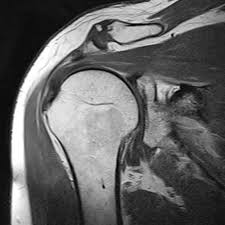

Myelopathie Schadigung Des Ruckenmarks Dr Christopoulos